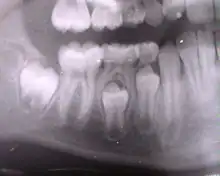

Radiographie panoramique permettant de voir l'ensemble de la denture (carie en distal de la dent no 35).